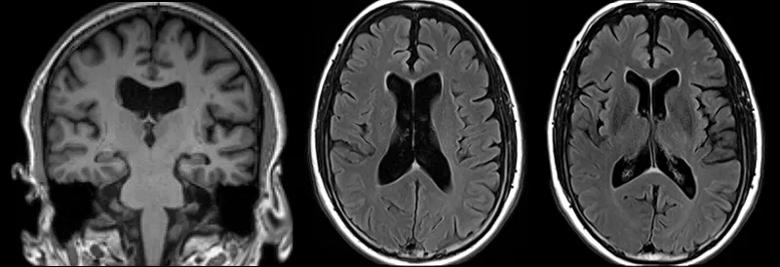

In March 2023, in hopes of resolving his quest for a definitive diagnosis, the patient elected to self-pay for a volumetric MRI at the Lou Ruvo Center for Brain Health. The volumetric analysis indicated that he had enlarged cerebral ventricles. Enlarged ventricles can be seen in normal pressure hydrocephalus, along with symptoms of Hakim’s triad — cognitive decline, gait disturbance and urinary incontinence. Normal pressure hydrocephalus, which is caused by cerebrospinal fluid (CSF) buildup in the brain, affects approximately 0.2% of people between 70 and 80 years of age. Since the patient now had its three primary symptoms, a diagnosis of normal pressure hydrocephalus was plausible.

three brain MRIs side by side against black background

Representative images from the patient’s volumetric brain MRI.